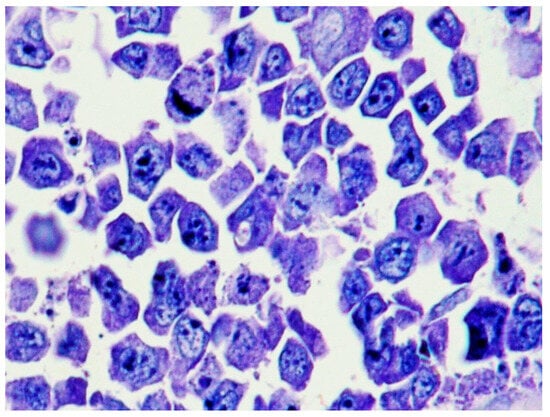

2.2. Morphology and Immunophenotype

3.4. Outcome and Treatment

| Histology | Large cells with IB and PB features | Diffuse proliferation of PBs/IBs | Sinusoidal and/or diffuse growth pattern of IBs and PBs | Sheets of PBs/IBs effacing organ architecture |

| CD20 | - (may be + in EC-PEL) | - or weakly + in a small number of cells | - (or weakly +) | +/− |